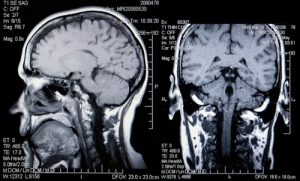

- МРТ